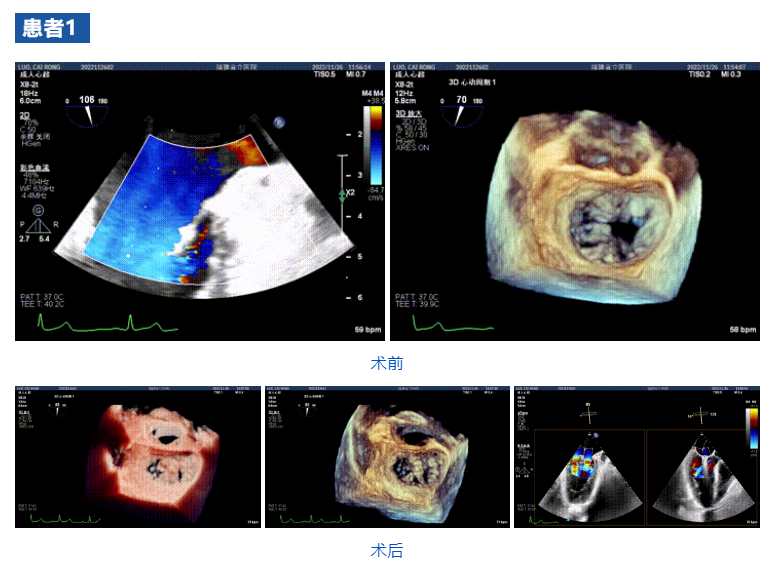

接受治療的三例患者均為器質性重度二尖瓣反流(DMR)患者,術前超聲提示二尖瓣后葉脫垂伴4+反流,左室舒張功能減退。郭延松教授攜同團隊成員陳新敬副教授和洪景宣、方明程、楊清勇主治醫師、心外科丁杭主任以及超聲科賴寶春、葉振盛主治醫師共同進行病情討論??紤]到患者高齡、基礎疾病多、STS評分高,為外科手術極高危患者,不適合進行外科開胸二尖瓣手術,因此決定為患者實施經導管緣對緣修復介入術(JensClip經導管瓣膜夾系統)。

在浙江大學醫學院附屬第二醫院王建安教授團隊的支持下,手術經股靜脈-房間隔入路,采用全身麻醉插管,在TEE和DSA引導下完成房間隔穿刺。置入JensClip瓣膜夾系統后,在左房調整瓣膜夾的位置和軸向,后進入左室,在TEE引導下捕捉二尖瓣前后瓣葉,并關閉瓣膜夾。經TEE反復確認手術效果后最終鎖定并釋放瓣膜夾。術后即刻超聲顯示瓣膜夾位置穩定,功能良好,二尖瓣反流由術前4+減少至微量,手術圓滿成功。